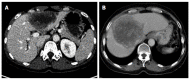

Aim: To establish a computed tomography (CT)-morphological classification for hepatic alveolar echinococcosis was the aim of the study.

Methods: The CT morphology of hepatic lesions in 228 patients with confirmed alveolar echinococcosis (AE) drawn from the Echinococcus Databank of the University Hospital of Ulm was reviewed retrospectively. For this reason, CT datasets of combined positron emission tomography (PET)-CT examinations were evaluated. The diagnosis of AE was made in patients with unequivocal seropositivity; positive histological findings following diagnostic puncture or partial resection of the liver; and/or findings typical for AE at either ultrasonography, CT, magnetic resonance imaging or PET-CT. The CT-morphological findings were grouped into the new classification scheme.

Results: Within the classification a lesion was dedicated to one out of five "primary morphologies" as well as to one out of six "patterns of calcification". "primary morphology" and "pattern of calcification" are primarily focussed on separately from each other and combined, whereas the "primary morphology" V is not further characterized by a "pattern of calcification". Based on the five primary morphologies, further descriptive sub-criteria were appended to types I-III. An analysis of the calcification pattern in relation to the primary morphology revealed the exclusive association of the central calcification with type IV primary morphology. Similarly, certain calcification patterns exhibited a clear predominance for other primary morphologies, which underscores the delimitation of the individual primary morphological types from each other. These relationships in terms of calcification patterns extend into the primary morphological sub-criteria, demonstrating the clear subordination of those criteria.

Conclusion: The proposed CT-morphological classification (EMUC-CT) is intended to facilitate the recognition and interpretation of lesions in hepatic alveolar echinococcosis. This could help to interpret different clinical courses better and shall assist in the context of scientific studies to improve the comparability of CT findings.